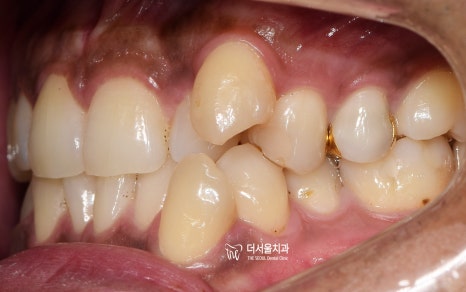

『초진 사진』

정면과 측면에서의 모습입니다.

치열의 불규칙성이 한 눈에 들어옵니다.

근데 단순히 이거 때문에 내원을 하셨을까?

아니죠.

정면에서 보는 안모사진을 보면,

얼굴의 중신선과 앞니들이

서로 일치하지 않는것을 볼 수 있습니다.